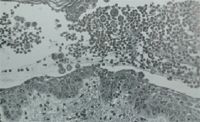

The immune system plays a role in the development of juvenile- and adult-onset demodicosis.